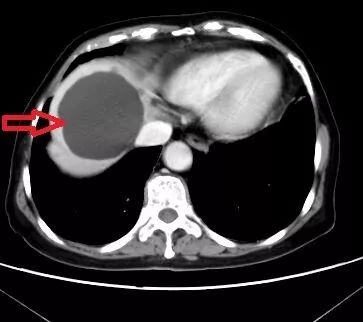

△患者巨大的肝囊腫

據(jù)悉,該患者78歲,因腹痛就診正興醫(yī)院,經(jīng)CT檢查發(fā)現(xiàn)肝臟一個達8公分大小的肝囊腫。巨大的肝囊腫導致患者經(jīng)常腹脹,腰部酸痛?;颊呤嗄昵霸诋?shù)匦心懩仪谐g,當時膽囊切除術后腹腔置管引流了四五天,一直有腹痛和血性液引流。因此,蘇軍凱博士判斷患者存在明顯的腹腔手術后常見粘連,腸子與腹壁或肝臟與膈肌粘在一起。